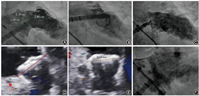

3例在完成LAA造影后,放弃尝试植入PLO,择期行LAmbre封堵器补救,2例成功(1例使用最大型号LAmbre封堵器36 mm×40 mm ,1例使用特殊型号LAmbre封堵器18 mm×32 mm,图10),1例使用2个LAmbre封堵器但仍封堵失败(图11)。

6例尝试植入PLO不成功,行补救性DLO植入,均成功封堵,使用LAmbre封堵器5例和Leftear封堵器1例。其中3例使用较大型号封堵器(图12),31 mm×35 mm 1枚(Leftear封堵器)和36 mm×40 mm 2枚,1例使用最小型号LAmbre封堵器(图13)16 mm×22 mm、2例使用特殊型号LAmbre封堵器24 mm×36 mm及22 mm×34 mm。

值得注意的是,发生冠状动脉压迫3例(0.5% ),均为PLO组(3/328, 0.9% ),且均为植入Lefort封堵器(3/81, 3.7% ),观察到患者出现胸闷症状及心电图改变。1例封堵器未释放,予全回收,观察到出现心包积液,中等量,未出现填塞,迅速再次植入Lefort封堵器,后观察症状稳定,未予心包穿刺,围手术期无其他并发症。2例在Lefort封堵器释放后发现压迫冠状动脉,造影提示1例压迫到左主干末端分叉处,行补救性PCI治疗[17];1例压迫到LCx近端,仅LCx行补救性PCI治疗(图14)。

封堵器脱落1例(0.2% )。患者植入22 mm×28 mm LAmbre封堵器,满足COST原则后释放封堵器,密封盘稍移位致出现>5 mm的残余分流,考虑封堵器可能存在脱落风险。使用Fustar可调弯鞘管(先健科技公司,深圳)及普通一次性活检钳回收封堵器时出现封堵器掉落,并进入降主动脉系统,顺利回收。并再次植入新的22 mm × 28 mm LAmbre封堵器1枚(图15)。